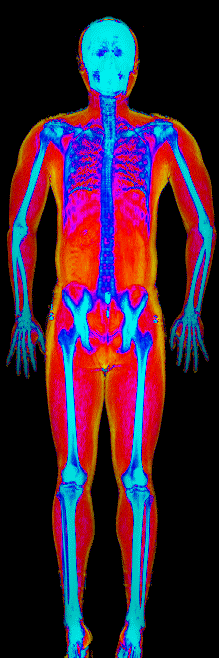

What Fat Loss Looks Like on a DEXA Scan

Lost 30.2 lb of fat, gained 3.9 lb lean · 240 → 214 lb · Age 43

Lost 27.9 lb of fat · 225 → 191 lb · Age 40

Lost 23.7 lb of fat · 186 → 155 lb · Age 34